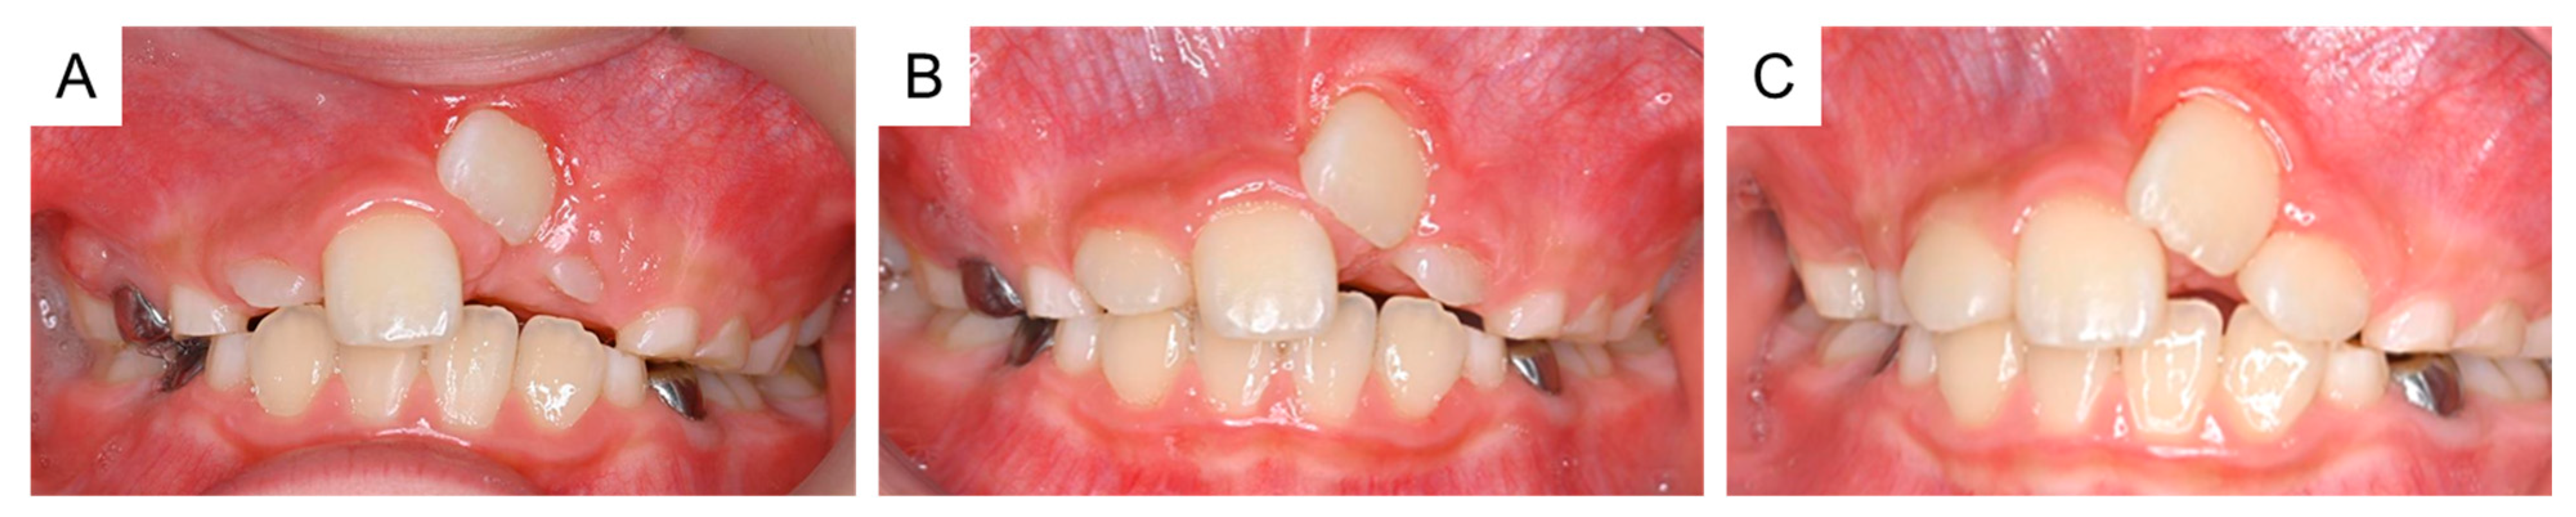

Figure 6. Intraoral photographs of the postoperative period. (A) One month after surgical exposure creation (8 years and 10 months of age). (B) Two months after surgical exposure creation (9 years and 0 months). (C) Four months after surgical exposure creation (9 years and 2 months).